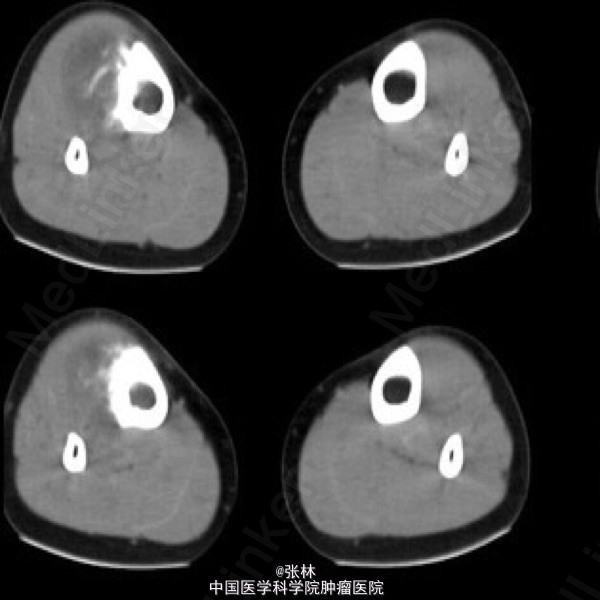

【病史临床】患者,女性,11岁,右侧胫骨上段触痛,血象及皮温不高。

影像表现:右胫骨外侧骨皮质表面低密度软组织肿块,与骨干长轴平行,基底部有条状钙化影,肿块边缘有骨膜新生骨,骨皮质内面未受侵犯,肿块与骨皮质间无透亮间隙。

术后病理结果:尤文氏肉瘤(IIb期)